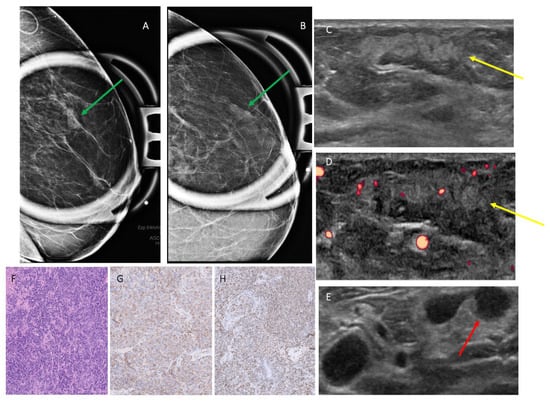

3.2. Mammographic Findings

3.3. Ultrasound Findings

3.4. MRI Findings

3.5. AI Analysis